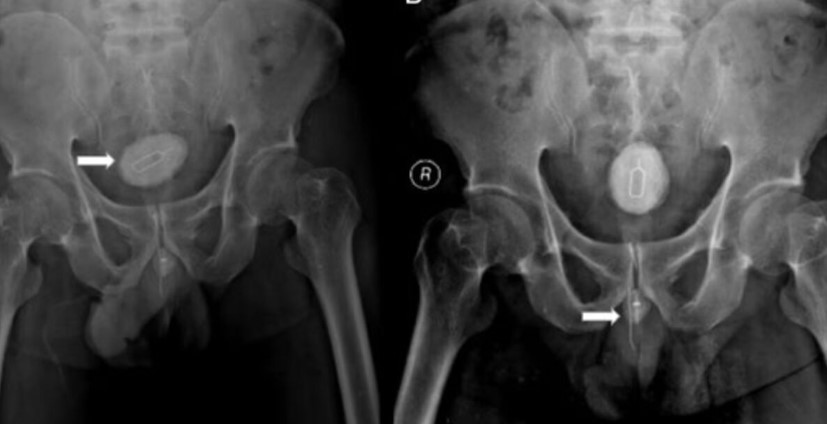

A radiografia da pelve do paciente mostrou um objeto opaco e uma “sombra” semelhante a um fio. Os médicos disseram que o objeto de metal levou o corpo a desenvolver uma espécie de pedra na bexiga do paciente.

A pedra chegou a medir 5×3 cm e foi retirada do corpo durante a cirurgia. O paciente também tinha um cabo elétrico de 10 cm e uma agulha de 8 cm amarrada com um elástico dentro do corpo, que também foram removidos.